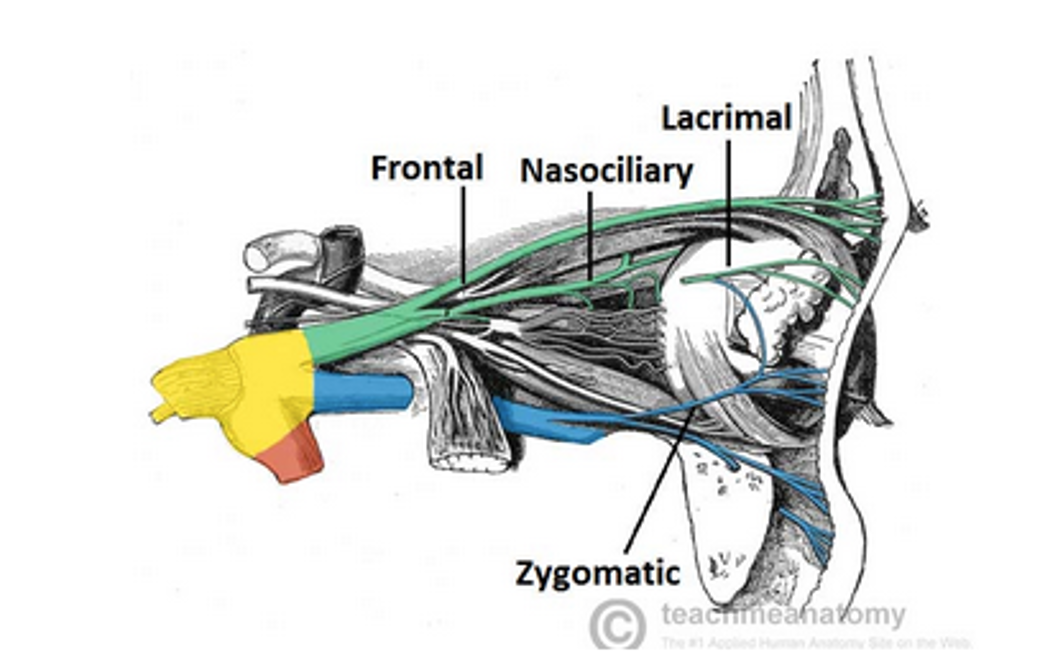

CN V1

- Lacrimal n.

- Nasociliary n.

- Ant./ Post. ethmoid n.

- 進入Ethmoid sinus

- Infratrochlear n.

- Long ciliary n.

- 瞳孔擴張

- Ant./ Post. ethmoid n.

- Frontal n.

- Supratrochlear n.

- Supraorbital n.